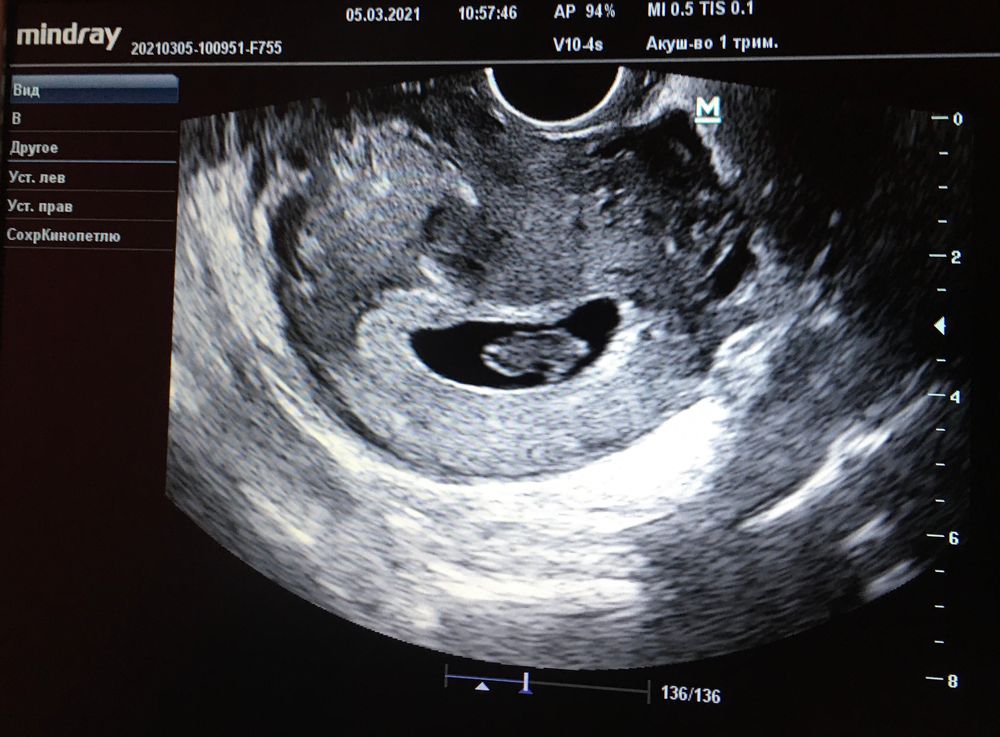

Вообще смотрят на хорион)

Это более белое "кольцо" на фото, вокруг плодного яйца.

Сейчас на фото, он уже кольцевидный. Это нормально и соответствует сроку)

Но большую локализацию я вижу слева получается на фото)